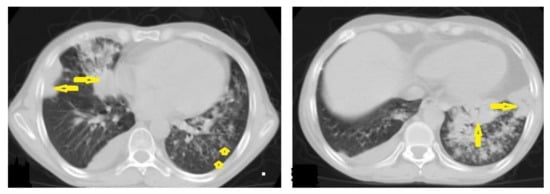

• Miliary TB (Figure 6 and Figure 7) appears as innumerable small (1–3 mm) granulomas with random distribution in the lungs and other organs with a predominance to the lung bases due to the gravity-dependent high blood flow. It occurs due to the hematogenous dissemination of mycobacterium tuberculosis bacilli, especially in immunocompromised patients and children [1,13]. Miliary TB is a significant differential diagnosis of pulmonary metastasis from thyroid cancer or others, even in children [19].

Figure 6. Miliary TB in an 18-year-old man (same patient of Figure 1). (a) Chest radiograph shows superimposed innumerable small nodules in lungs right greater than the left predominantly affecting lung bases due to gravity-dependent high blood flow. (b) Axial chest CT shows innumerable small (1–3 mm) nodules with random distribution in both lung fields.